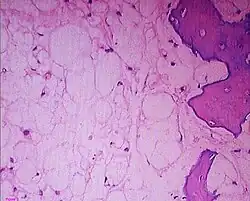

Obraz histologiczny struniaka. Widoczne duże zwakuolizowane komórki i miejscowa destrukcja tkanki kostnej[1]

Struniak (łac. chordoma, ang. chordoma) – rzadki, wolnorosnący nowotwór złośliwy, wywodzący się z pozostałości struny grzbietowej. Pozostałości struny znajdują się najczęściej na stoku (clivus) kości potylicznej i w okolicy krzyżowo-guzicznej, i tam też najczęściej rozwija się struniak. Guz trzykrotnie częściej występuje u mężczyzn. Rozwija się zazwyczaj w średnim wieku, najczęściej w 4. dekadzie życia. W Stanach Zjednoczonych zapadalność roczną na struniaka szacuje się na 1:1 000 000, co daje 300 nowych zachorowań co roku w tym kraju.